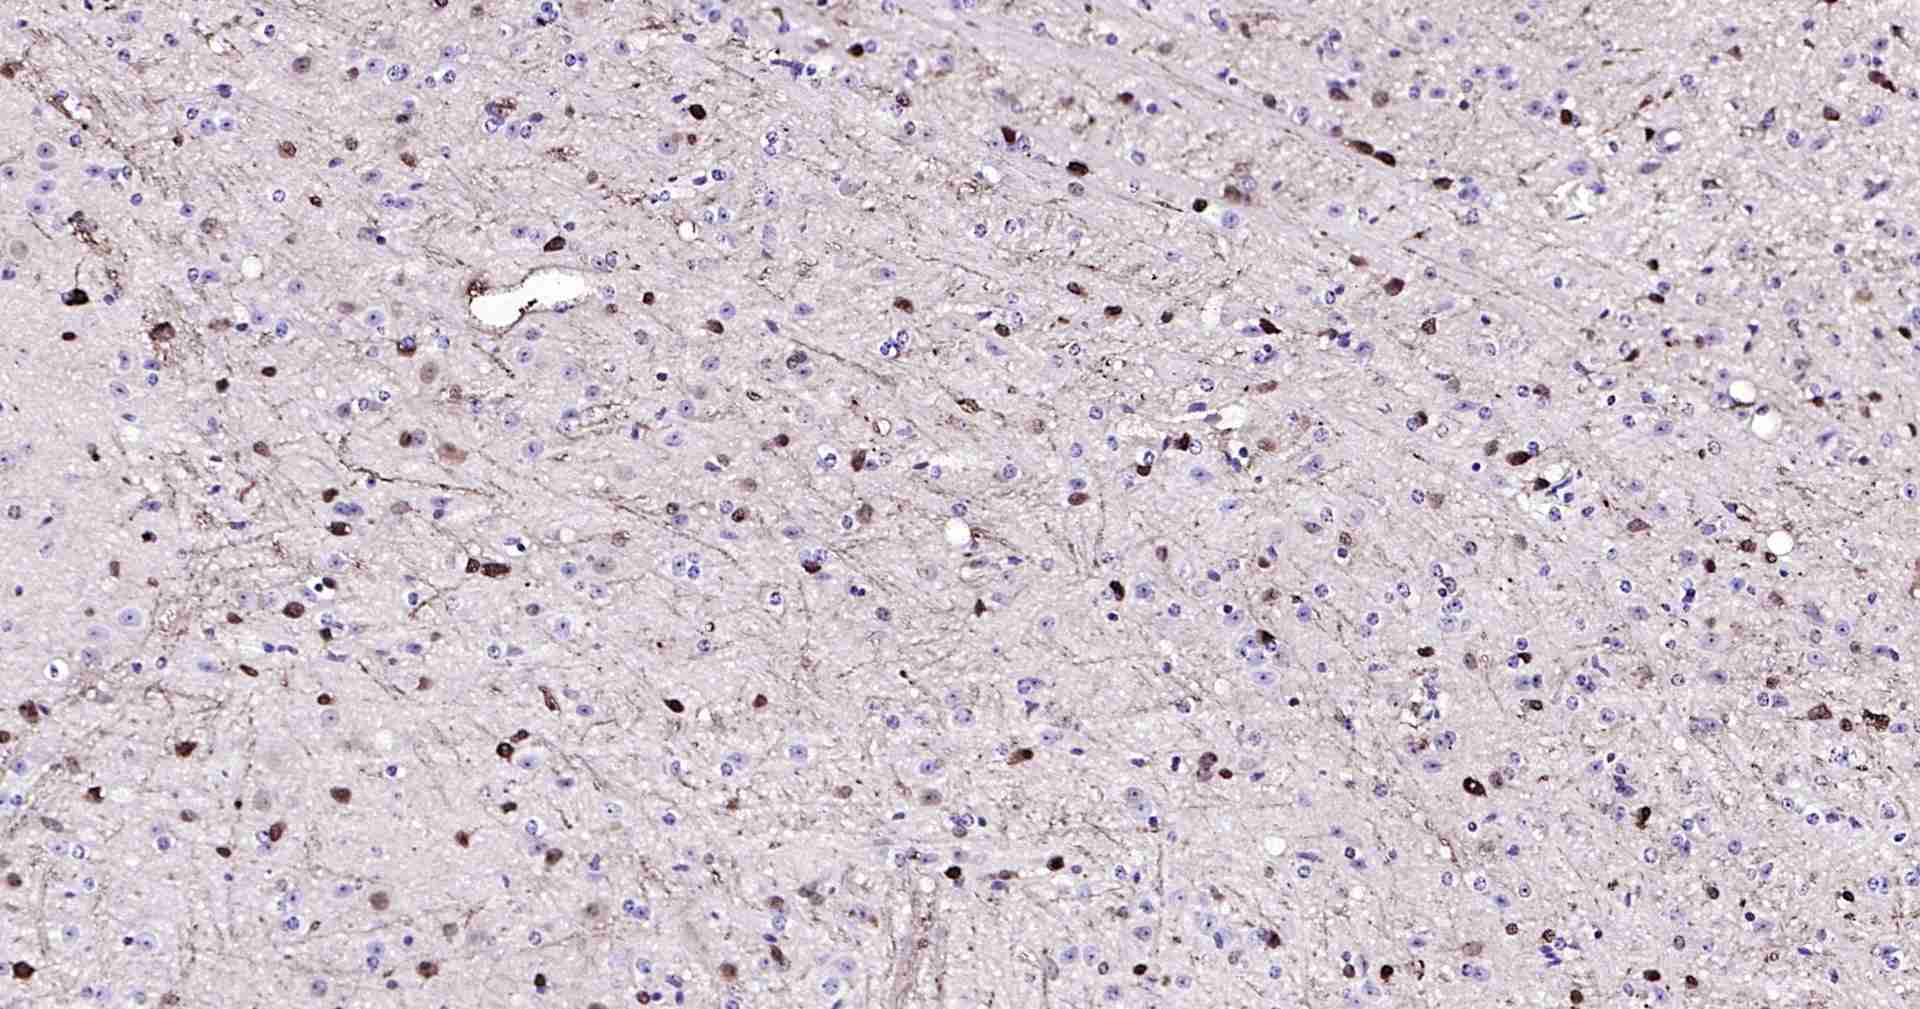

Bioss推出的系列超敏二步法免疫组化检测试剂,它将多聚辣根酶复合物(Polymer-HRP)和二抗抗体分子聚合在一起,替代传统方法中的二抗和三抗,直接放大抗原抗体结合的信号,既保留了抗体特异性结合抗原的能力,又可有效的避免聚合分子过大而造成的空间位阻。此试剂盒与传统的SP三步法相比,具有简单、快速、敏感等特点,因为系统中不再使用生物素,所以避免了由于内源性生物素所造成的背景染色。本品独特的Polymer-HRP有利于大分子的检测系统更好的结合所检测的一抗分子,此检测系统是目前已知的灵敏度最高的系列免疫组化检测系统。

此外,本试剂盒还提供了内源性过氧化物酶阻断剂工作液,可抑制内源性过氧化物酶的活性,达到降低背景染色的目的;另提供了正常山羊血清封闭工作液,因二抗可能会与组织中的内源性免疫球蛋白发生交叉反应,使用二抗宿主来源的非免疫血清预处理该组织,可最大程度减弱此反应。

7、使用DAB显色液显色,蒸馏水清洗切片以终止反应。

8、如果需要,可进行苏木素复染、脱水、透明、封片、镜检。